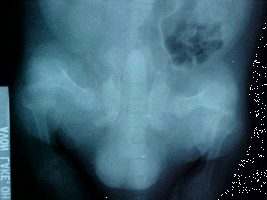

X-ray showing poor bone density X-ray showing improved bone density

Poor Bone Density Good Bone Density

Malnutrition, poor diet (green bean's, pea's, lettuce); X-rays show very little bone mass or muscle, bones thin and brittle like egg shell, severely deformed legs.

Treatment: Morning: 1/8 tsp. Rep-Cal powder, 1/2 squirt liquid taurine, pinch Echinacea (first three weeks to build up his immune system), 1/3 cup thawed frozen veggies, 10 Cheerios or soy cereal. Lunch: 1/2 cc Pet Tinic (for 4 weeks), 1/8 - 1/4 tsp. colostrum, 1/8 tsp. whey powder, 1 tbsp. skunk mixture, sardines, or salmon; 1 tsp. low fat yogurt. 3:00 PM: Vitamin K, fresh vegetables, 1/8 tsp. Vitamin C, tofu or raw oats. Supper: 1/8 tsp. Rep-Cal., dab of Feliobite II, 1/8 tsp. whey powder, fresh veggies, chicken or Skunk mixture, 1 tsp. low fat yogurt, blueberry, apple or pear (small amount). Nighttime snack: four small pieces of Bil-Jack dog food. Used Reptile Light [UV+ lamp] for 15 minutes per day while eating. X-rays in 58 days show remarkable regrowth in bones. Still badly deformed. Added 1/4 tsp. Synovi-MSM and B-complex to diet twice daily, dropped the whey to 1/8 tsp. daily.